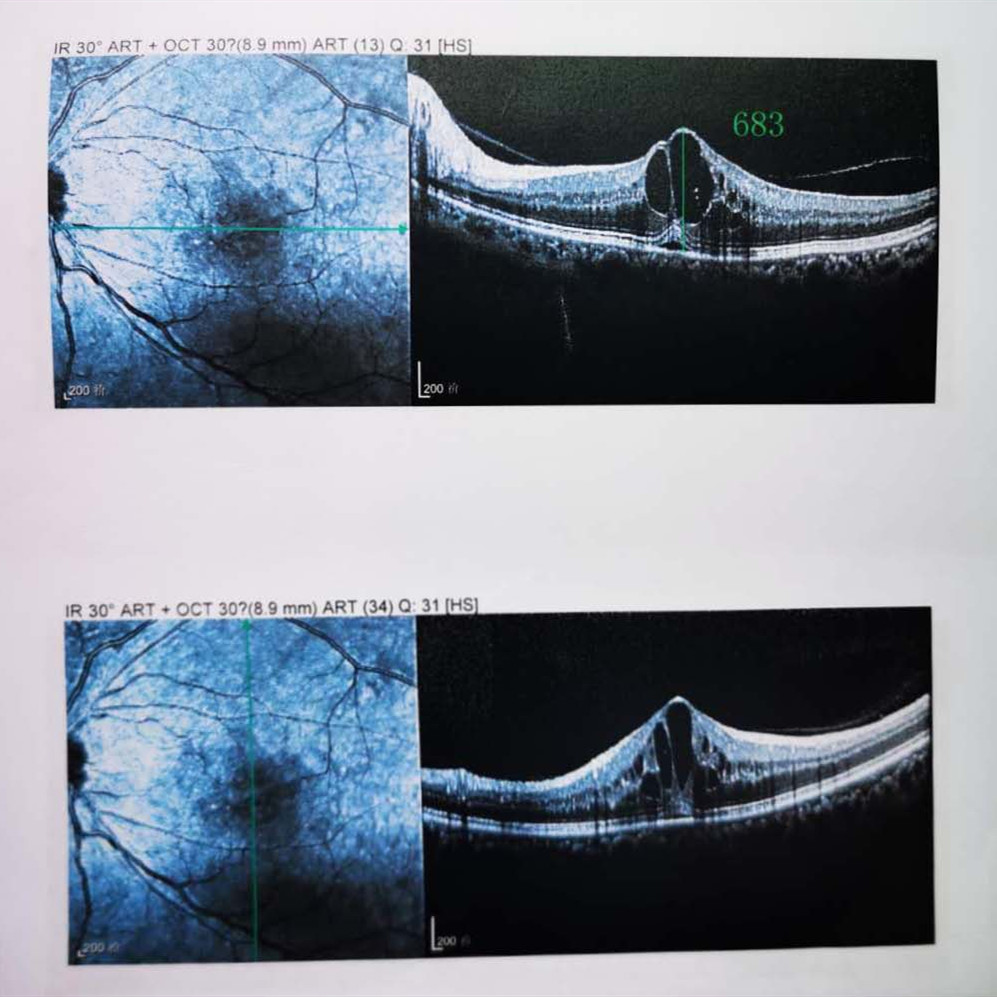

檢查結(jié)果顯示,武先生并沒(méi)有近視,右眼視力為1.0,但是左眼視力只有0.4,而且左眼視網(wǎng)膜各分支靜脈迂曲擴(kuò)張,全網(wǎng)膜面見(jiàn)火焰狀出血,黃斑區(qū)高度水腫、滲出,黃斑中心凹厚度約683um。

(武先生初次就診眼底OCT檢查圖)

而正常的矯正視力是1.0,黃斑中心凹厚度在200um左右。

“你這黃斑都腫到正常人的三四倍大了!”廈門(mén)眼科中心吳國(guó)基院長(zhǎng)醫(yī)生告訴武先生,“你這是左眼視網(wǎng)膜中央靜脈阻塞伴黃斑水腫,你左眼的視力下降、看東西變形,是因?yàn)槟阕笱垡暰W(wǎng)膜的中央靜脈發(fā)生了阻塞、出血,導(dǎo)致眼底黃斑水腫了。”

那么,武先生的視力恢復(fù)情況如何呢?幸運(yùn)的是,經(jīng)過(guò)兩次玻璃體腔注藥術(shù),武先生左眼的黃斑水腫得到明顯改善,視力已經(jīng)恢復(fù)到0.8。

(武先生出院時(shí)眼底OCT檢查圖)